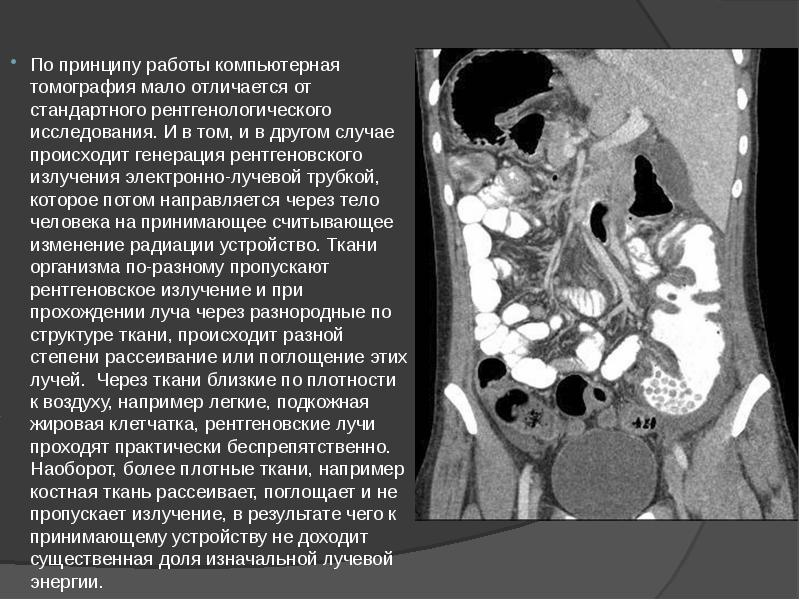

- 3. По принципу работы компьютерная томография мало отличается от стандартного рентгенологического исследования.